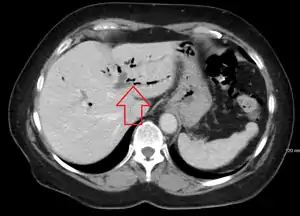

Pneumobilia is the presence of gas in the biliary system. It is typically detected by ultrasound or a radiographic imaging exam, such as CT, or MRI. It is a common finding in patients that have recently undergone biliary surgery or endoscopic biliary procedure. While the presence of air within biliary system is not harmful, this finding may alternatively suggest a pathological process, such as a biliary-enteric anastomosis, an infection of the biliary system, an incompetent sphincter of Oddi, or spontaneous biliary-enteric fistula.

| CT scan of pneumobilia |